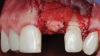

A patient presented for the restoration of an implant that had been placed at the site of tooth No. 9, which exhibited a residual soft-tissue deficiency and an undulating facial soft-tissue morphology (Figure 11). The objective of the treatment was to change the appearance and thickness of the facial soft tissue prior to crown placement to optimize the esthetics and prevent future soft-tissue dehiscence. After flap reflection (Figure 12), a graft was acquired from the patient's tuberosity to augment the supracrestal soft tissue (Figure 13). A volume-stable collagen matrix was then placed to further increase the thickness of the soft tissue adjacent to the implant body (Figure 14), and the flap was sutured closed (Figure 15). Following a 3-month healing period, a positive change in the soft tissue's morphology was apparent; however, its volume remained deficient when compared with that of tooth No. 8 (Figure 16). When the screw-retained crown was delivered, a second graft was acquired from the tuberosity and placed to further increase the volume of the supracrestal soft tissue (Figure 17 and Figure 18). A postoperative healing period of 4 months resulted in an ideal position of the margin of tooth No. 9 with regard to its contralateral counterpart as well as more natural looking soft-tissue morphology and excellent supracrestal soft-tissue thickness (Figure 19 and Figure 20). Eight months postoperatively, the position of the gingival margin and the thickness of the soft tissue had been maintained (Figure 21 and Figure 22).

(12.) Flap reflection to assess the position of the coronal aspect of the implant and facilitate soft-tissue grafting.

Figure 12

(13.) A soft-tissue graft from the tuberosity was placed to augment the supracrestal soft-tissue.

Figure 13